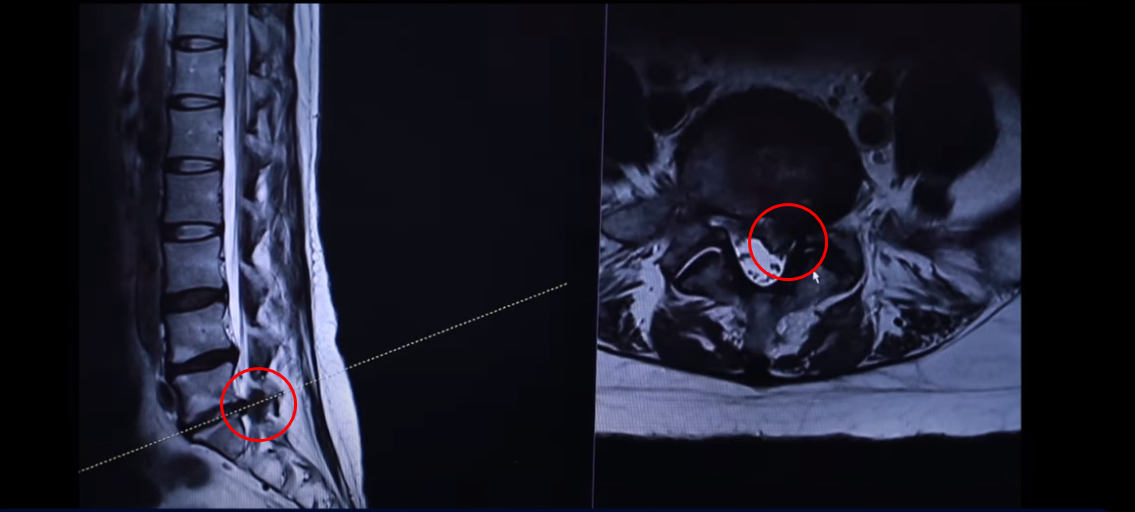

주사도 놔주지 않습니다. 주사가 전혀 의미가 없을 거라고 얘기하고 ‘무조건 수술을 해야 된다’ 이렇게 얘기를 듣습니다. 그런데 이분의 친언니 분이 있는데 그 친언니 분이 한 2년 전에 저희 모커리한방병원에서 허리디스크 파열로 치료를 받으셨습니다. 근데 친언니분도 MRI 디스크 터진 게 완전히 똑같습니다. 그분도 치료 후기를 이렇게 찍으셨는데요. 그분 MRI를 여기서 다시 한 번 보실까요?

이게 그 언니분 MRI인데 언니분도 5번 1번 정확히 왼쪽으로 터져 있습니다.

그래서 디스크가 유전이 관련돼 있다, 디스크란 질환이 그게 어느 정도 이런 걸 보면 알 수가 있습니다. 수많은 마디 중에 동생분도 이렇게 세 마디가 퇴행이 돼 있습니다. 맨 마지막 마디가 왼쪽으로 밀려나간 거 정확히 똑같습니다. 이분도 한 2년 전에 저희 병원에서 입원 집중 치료받고 완전히 좋아지셨습니다. 그래서 지금 일상생활 잘하고 계시고 이 치료후기 안에서 그 부분에 대해서는 동생분이 얘기를 합니다.

다시 동생분 MRI로 돌아가겠습니다. 언니분하고 똑같이 이 동생분 세 마디 디스크가 퇴행돼 있죠 그리고 마지막 마디가 터져서 이렇게 왼쪽으로 심하게 밀려 나가 있습니다.

언니분보다 터진 정도는 더 심합니다. 그래서 이렇게 디스크가 심하게 파열되고 또 마비 증상까지 있는 분들 이런 분들은 이 환자분이 들으신 것처럼 정형외과나 신경외과에서 즉시 수술을 해야 된다. 또 마비 증상까지 있으니까 바로 수술을 하지 않으면 마비 증상이 오래되면 신경이 심하게 눌려 있으면 신경 기능이 많이 떨어지면 만약 마비가 풀리지 않는다고 그러면 그건 이제 장애가 되는 거죠. 그렇기 때문에 즉시 수술을 해야 된다 이렇게 듣는데 이렇게 파열이 심한 분들일수록 저희는 오히려 비수술 재활 치료가 성공할 확률이 더 높다. 역설적이게도 파열이 심하면 심할수록 치료가 더 잘될 확률이 높다. 저희 모커리한방병원이 이렇게 설명을 하고 있는데 왜 그럴까요?